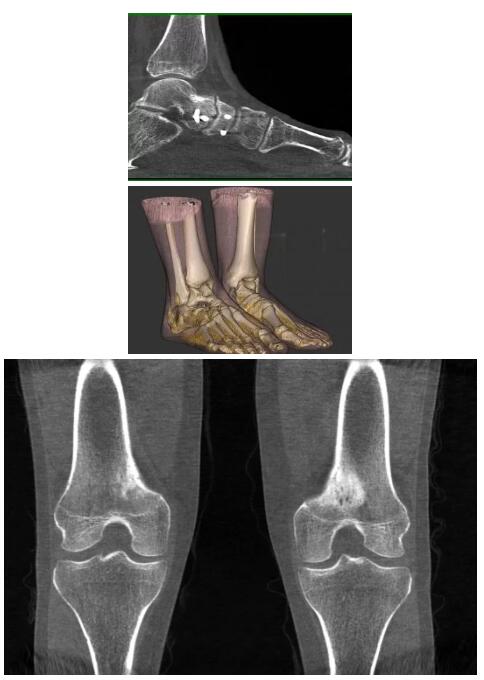

比如上面這款專用于足部和踝部掃查的CT成像系統(tǒng),患者在進行CT掃查時只需要站在上面即可,雙腳站或者單腳站都可以,當(dāng)然,如果患者不是那么方便站著做完CT掃查,也可坐在上面。

這款CT掃查系統(tǒng)自帶屏蔽裝置,它的體積非常小,僅需要極小的空間即可,并不像常規(guī)CT那樣需要一間單獨的檢查室。此外,這種CT掃查的速度非???,僅需30秒左右可以完成檢查,輻射劑量相對常規(guī)的CT要少許多,尤其適合醫(yī)院的骨科使用。

而患者站著做足部或者踝部做CT檢查還有個好處是,可以檢查患者在負重的情況下,骨關(guān)節(jié)的真實情況,而躺著做CT掃查時未必能看出來。負重CT掃查特別是對于受傷的運動員或者舞蹈員來說意義更大,能夠更準確地評估傷情,幫助他們盡早復(fù)原。

以上介紹的CT均來自國外同一家公司,這些CT均配置了可視化軟件,可以進行切片、3D重建以及大型CT附帶的所有典型的操作功能。

以下是這些“特立獨行”的CT所拍出來的圖像: